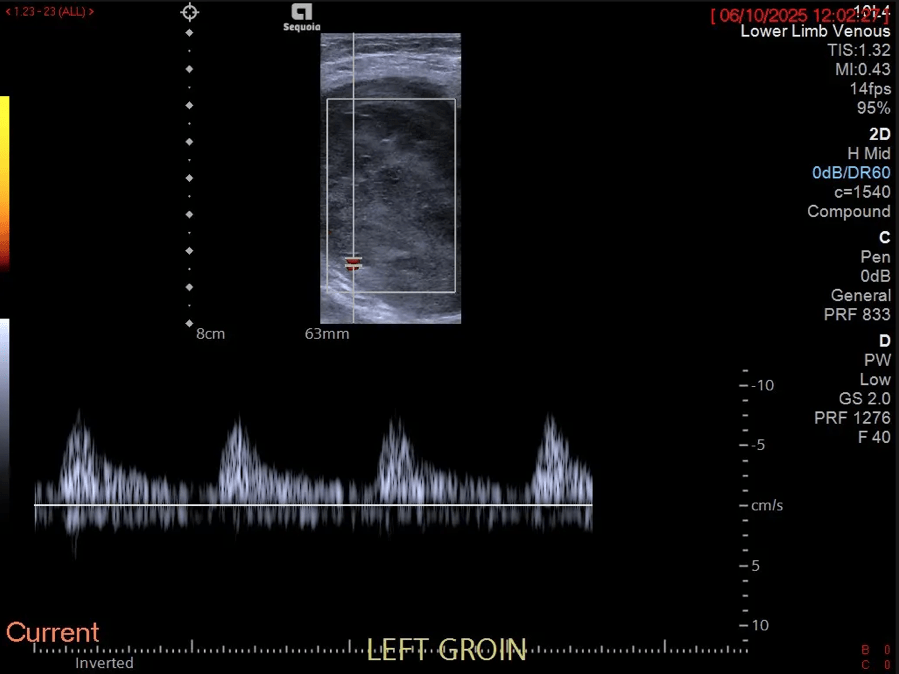

Fig. 03. Transverse pulse-wave Doppler imaging, targeted on an intra-lesional vessel, demonstrates arterial flow. The Doppler gain was increased, and the scale was reduced to maximise vascular signal from the central portions of the tumour, thereby producing an image with increased noise.